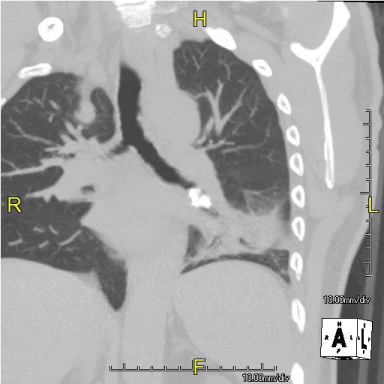

He was seen in our office in consultation. He appeared well. Vitals were stable. There was no clubbing of fingers or lymphadenopathy. Chest exam revealed decreased breath sounds over the lower left chest posteriorly with bronchial breath sounds and aegophony. Remainder of his examination was normal. Lab testing including a CBC, HIV test and immunoglobulin profile was unremarkable. Pulmonary function testing was normal. A Computed Tomography (CT) of the chest was obtained and representative cuts are shown (Figure 1,2). A bronchoscopy showed a smooth lobulated mass occluding the left lower lobe orifice. Endobronchial biopsies were obtained and showed features suggestive of a chondroid hamartoma (Figure 3). Resection of the lesion was planned because of repeated pulmonary infections.

Figure 1. Mass with calcification, Left lower lobe bronchus

Figure 2. Mass in left lower lobe bronchus